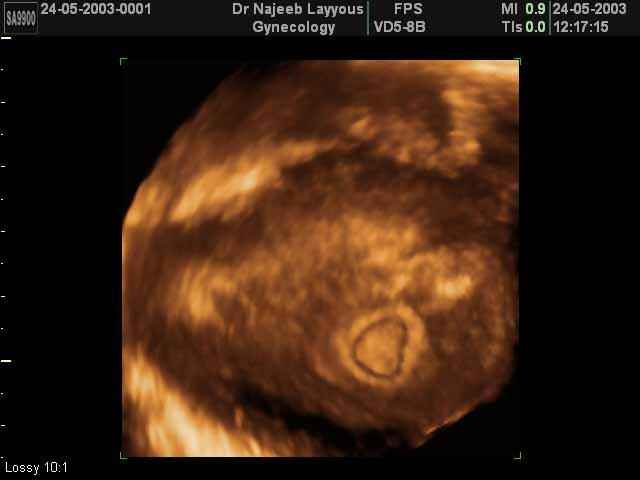

- 3D Photos Ecographie du Premier Trimestre